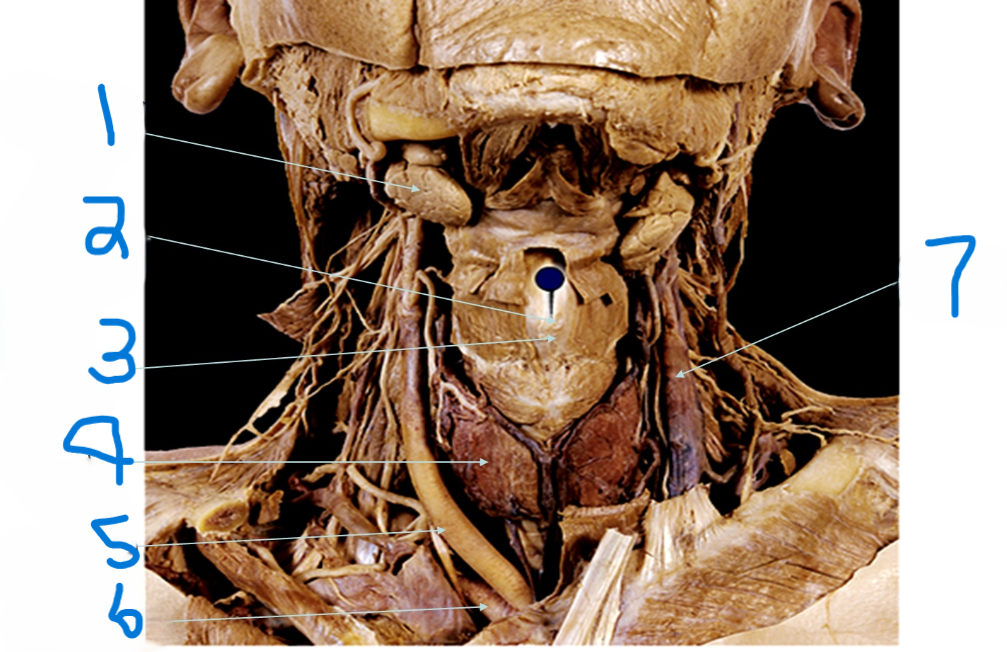

What is depicted by #1

Laryngeal Prominence (adams apple)

What is depicted by #2

Thyroid cartilage

What is depicted by #3

Thyroid gland

What is depicted by #4

Right common carotid artery

What is depicted by #5

Right subclavia artery

What is depicted by #6

Left internal jugular vein

What is depicted by #7